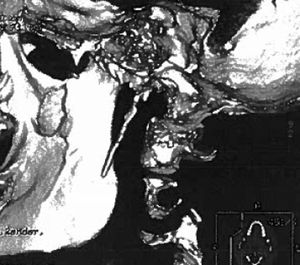

ResultsPatient 1Patient 1 was a 19-year-old man with a 3-year history of dull pain on the left side of the neck. Pain fluctuated in intensity, with exacerbations, and occasionally radiated to the ear, causing odynophagia and foreign body sensation in the pharynx. Pain intensity increased progressively, reaching an intensity of 8/10 on the visual analogue scale (VAS). The patient did not present nausea, vomiting, phonophobia, photophobia, ptosis, pupillary changes, tearing, or conjunctival injection, and pain was not exacerbated by exertion. The main trigger factors were forced opening of the mouth and yawning. A general and neurological examination revealed no remarkable alterations except for intense pain upon compression of the left tonsillar fossa. Results from a complete blood count, biochemical analysis, and coagulation study were normal. The patient tested negative for syphilis, Borrelia, and HIV. A head and neck MRI scan, scintigraphy, and Doppler ultrasound of the supra-aortic trunks revealed no alterations. Symptoms did not improve with indometacin, carbamazepine, valproate, flunarizine, or beta blockers. The patient underwent a skull base CT scan due to suspicion of stylalgia (Eagle syndrome). CT images revealed elongation of the left styloid process, which measured approximately 50mm (Fig. 1). Given the lack of response to several years’ conservative treatment, the styloid process was surgically removed, and symptoms resolved. The patient remains asymptomatic after 2 years of follow-up.

In terms of imaging studies, a CT scan of the neck and skull base (with 3D reconstruction, where possible) constitutes the optimal technique not only for estimating the length and thickness of the process but also to determine its anatomical relationship with muscles and blood vessels.